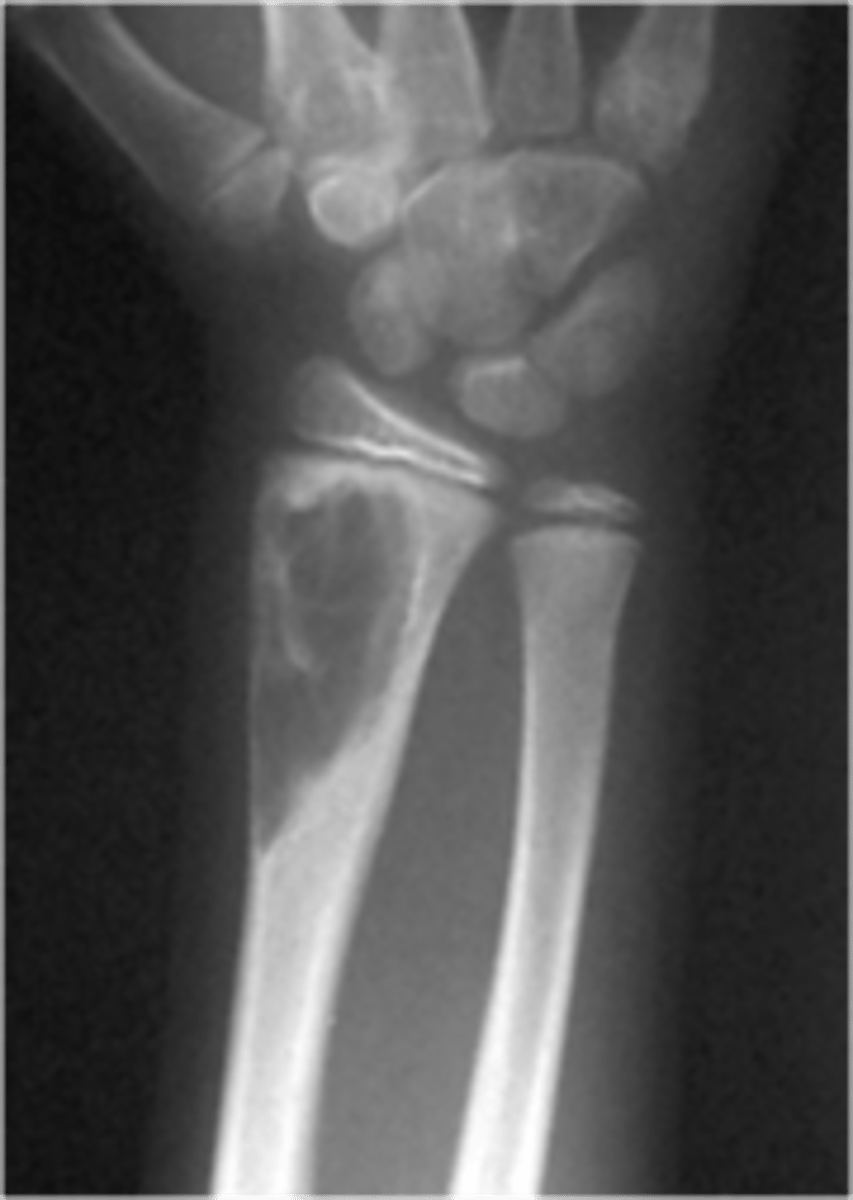

PA Wrist

Lateral wrist